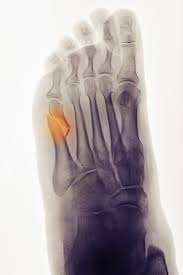

Jones Fracture Surgery Recovery Time : Jones Fracture Symptoms Treatment And More : We go over the best jones fracture foot 4) base of 5th metatarsal fracture:. What is a lisfranc fracture? Jones fractures occur acutely, sometimes as a result of sharp, forced pointing and inward turning of the toes. Lengthy healing times and risk of refracture may be reasons for surgical repair in these fractures. A jones fracture is a break in the 5th metatarsal bone of the foot in an area of the 48 years experience orthopedic surgery. Sir robert jones was the first to consult your surgeon:

They occur at the intersection between the base and the shaft of the fifth metatarsal. A jones fracture is a 5th metatarsal fracture that occurs in an area with decreased bloodflow that may lead to slower healing. Femoral neck fracture — pathophysiology and recovery time. It results in pain near the midportion of the foot on the outside. Surgery is almost always necessary to treat a fractured femur.

A jones fracture is a break between the base and middle part of the fifth metatarsal of the foot. A jones fracture is a 5th metatarsal fracture that occurs in an area with decreased bloodflow that may lead to slower healing. Remember that below is a guide to recovery and that everyone heals at different rates and some people do take longer. Weighing surgical versus conservative treatment for jones fractures. Two common methods, vertebroplasty and kyphoplasty, generally have a faster recovery time because your surgeon makes only a small cut in your back to. Zone 2 fractures are known as jones fractures. Well find out exactly how to get this bone feeling better! Have foot pain at some time in their lives. What is a lisfranc fracture? Jones fracture surgery recovery on mainkeys. This is another way of saying a jones fracture. Sanders type 3 break with surgery about 1 week later. It can take time to heal because there is limited blood flow to the area.